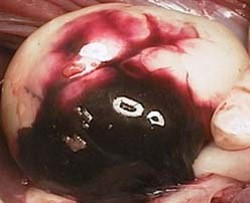

Focal area of dark red to black fluid found on the surface of this kidney. 5x5cm. Irregular demarcation.

Acute focally extensive severe traumatic haemorrhage of the kidney